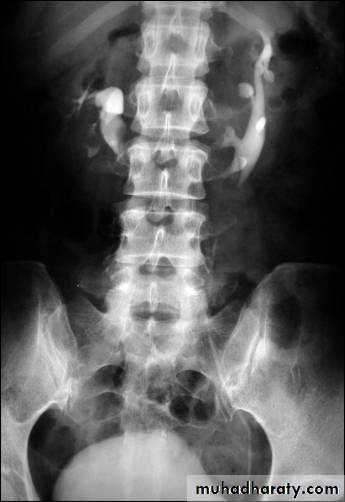

Horse shoe kidney -Kidneys may fail to separate.

-Almost invariably the lower poles remain fused.

-The kidneys axes are more parallel to the spine and malrotated.

-Diagnosis can be made by plain x-ray in some cases.

-US, CT scan and MRI can better demonstrate the anatomy and morphology hence the diagnosis.

-May be an incidental finding.

-PUJ obstruction and calculi formation are common .

IVU shows

1. The kidneys at low position .

2.Close to the spine with long axis parallel to the spine .

3. Malrotation manifested by medially directed calyces.

4- The renal pelvis and ureters are anterior and lateral in position .